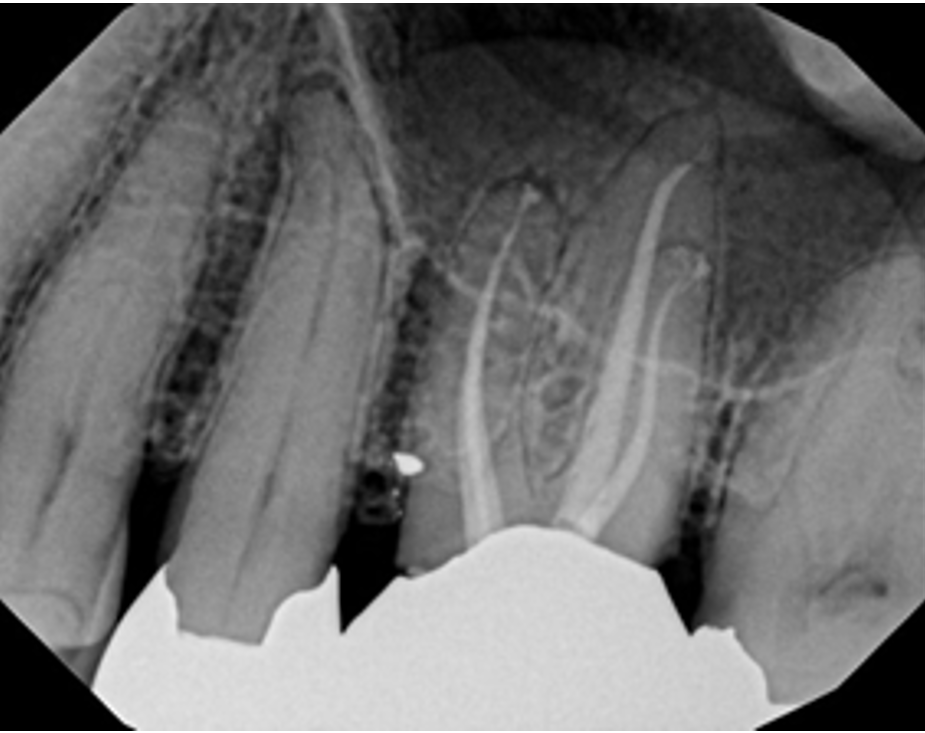

Examples of X-Ray scoring

(Group A – Odne Clean)

Score 4 – Simple anatomy with apical delta // Score 6 – Curved anatomy + lateral canal in middle third

Score 7 – Curved anatomy + lateral canal in apical third // Score 8 – Curved anatomy with apical delta